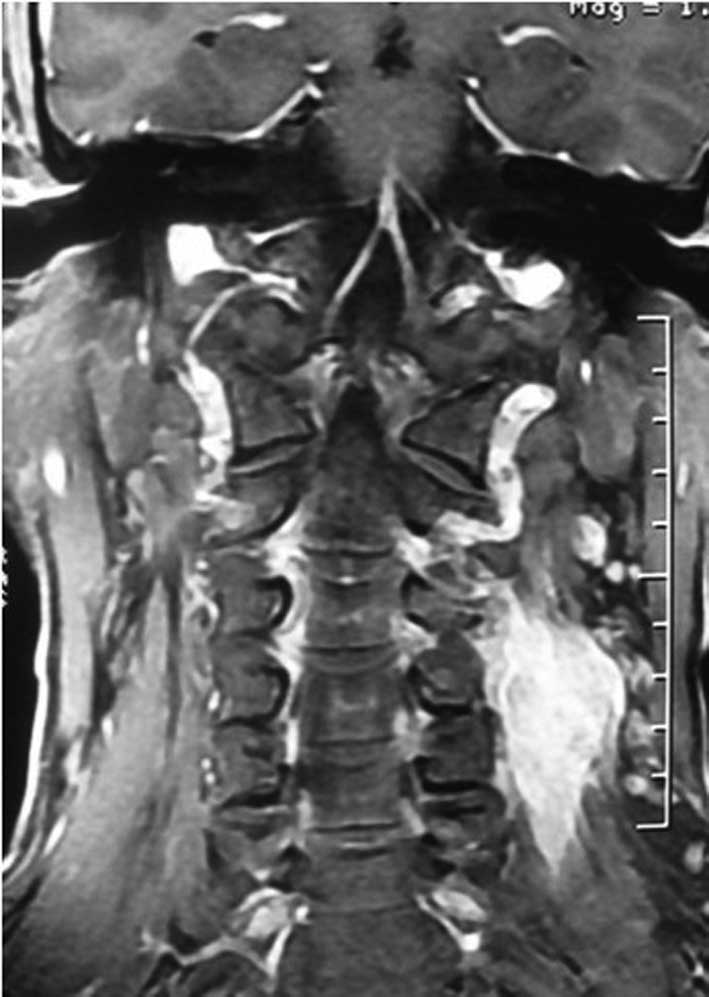

Primary dumbbell-shaped Ewing's sarcoma of the cervical vertebra in adults: Four case reports and literature review

Ewing's sarcoma is the second most common malignant bone tumor in children and adolescents. The 4 cases described in this study were diagnosed with dumbbell-shaped intraspinal and extraspinal Ewing's sarcomas. The incidence of dumbbell-shaped tumors of this type in the spine is 17.5%. These tumors are often misdiagnosed as neurogenic tumors (schwannoma, neurofibromatosis) or giant cell tumors based on imaging. Radiculopathy is more common than spinal cord compression in Ewing's sarcoma. Preoperative biopsy is strongly recommended. As soon as Ewing's sarcoma is diagnosed by pathology, the treatment should begin with 2-3 cycles of neoadjuvant chemotherapy. Anterior-posterior and posterolateral approaches are both recommended for exposing this tumor. Following surgery, chemotherapy is critical to lessen the rate of recurrence and metastasis and to prolong the survival time. However, radiotherapy should be used with caution, as the spinal cord is sensitive to radiation; local irradiation is suggested. The tumor is difficult to remove en bloc in the cervical spine. It has a high rate of recurrence and metastasis. Therefore, the prognosis of Ewing's sarcoma in the cervical region is poorer compared to that in the thoracic and lumbosacral regions.